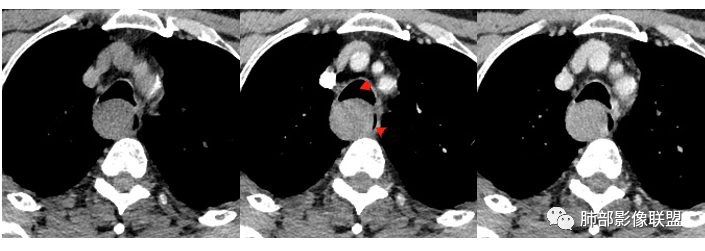

4.肿块渐进性强化,局部可见低强化区(下图红箭头所示),可以符合神经鞘瘤AB区的影像特点,尽管该部位神经鞘瘤罕见,毕竟食管壁也是有神经走行的,解剖也提示诊断的方向。

须排除的是平滑肌瘤及间质瘤。血管瘤及囊肿因强化方式不支持。